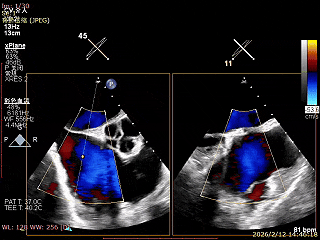

三尖瓣术前评估

三尖瓣反流(重度);肺动脉高压(中度);二尖瓣反流(中度);双房左室增大;左室顺应性减低。

术前食道超声评估

三尖瓣关闭不全重度(4+,平均缩流颈10mm),反流口以前隔、中央为主,部分后隔,瓣叶未见明显脱垂及GAP,三尖瓣环扩张(瓣环平均径43mm),二尖瓣中-重度反流,肺动脉高压(PASP:44mmHg)。